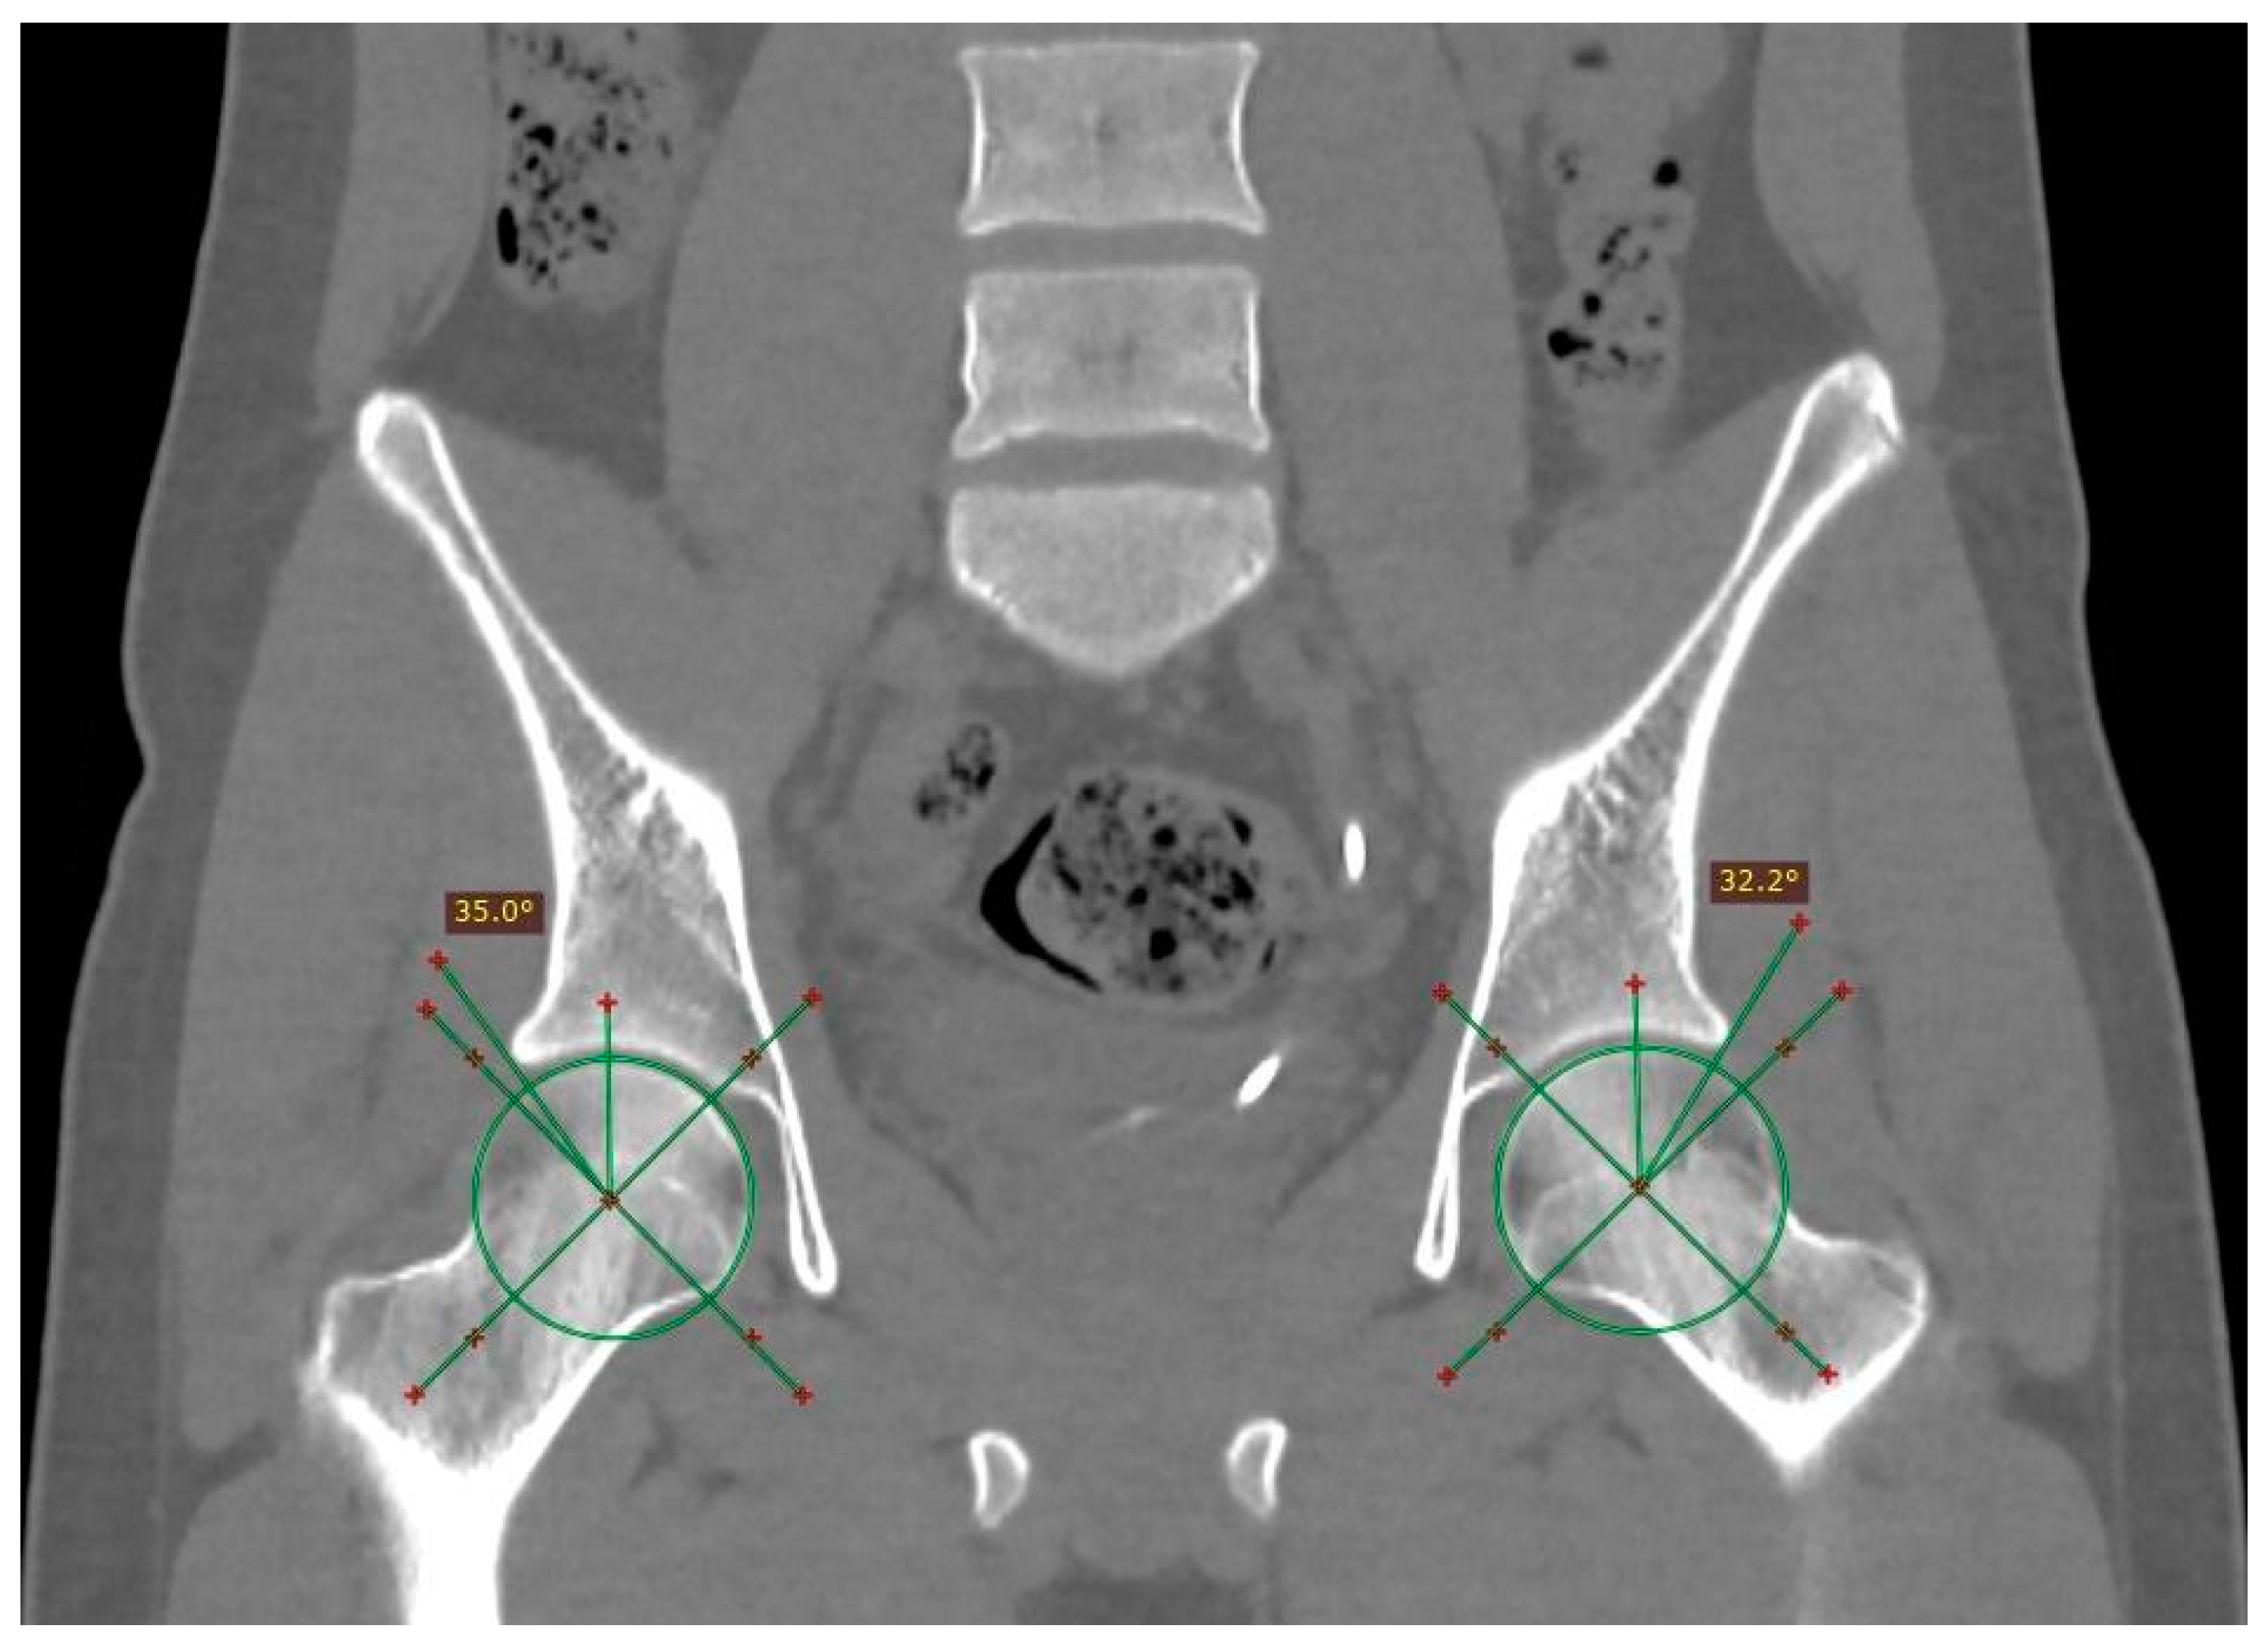

The anthropometric data revealed a general average height of 1.53 m and weight of 68.26 kg (SD ± 14.3). With respect to BMI, the mean was 29 (SD ± 14.3). Of the total patients, 47% presented morphological changes in femoroacetabular impingement, of which 37 correspond to the pincer-type, 17 to the cam-type, and 7 to the mixed-type (an example of mixed-type is shown in Figure 1).

Figure 1.

Computed tomography image with 3D volumetric reconstruction showing anterosuperior bony prominence in the cervical–cephalic transition of the bilateral femur, as well as bone excrescence in the right acetabular roof. Findings in relation to right mixed-type and left cam-type femoroacetabular impingement are marked with white arrowheads.

Patients who had compressive symptoms more often presented with C-sign, mixed impingement with 16.66% differences in Wiberg’s angle in patients with and without C-sign; furthermore, the average of the angles was greater in patients with C-sign, with a difference of 0.8112 degrees in the right angle and an even more pronounced difference between the averages of the left angle, at 2.7715 degrees (measurement of the Wiberg angle is depicted in Figure 3).

Figure 3.

Measurement of the center-edge angle (Wiberg) in an asymptomatic patient. An angle is obtained starting from the center of the femoral head, with a stroke following the vertical axis of the same (90°) and the lateral edge of the acetabulum. The normal value is less than 40°.